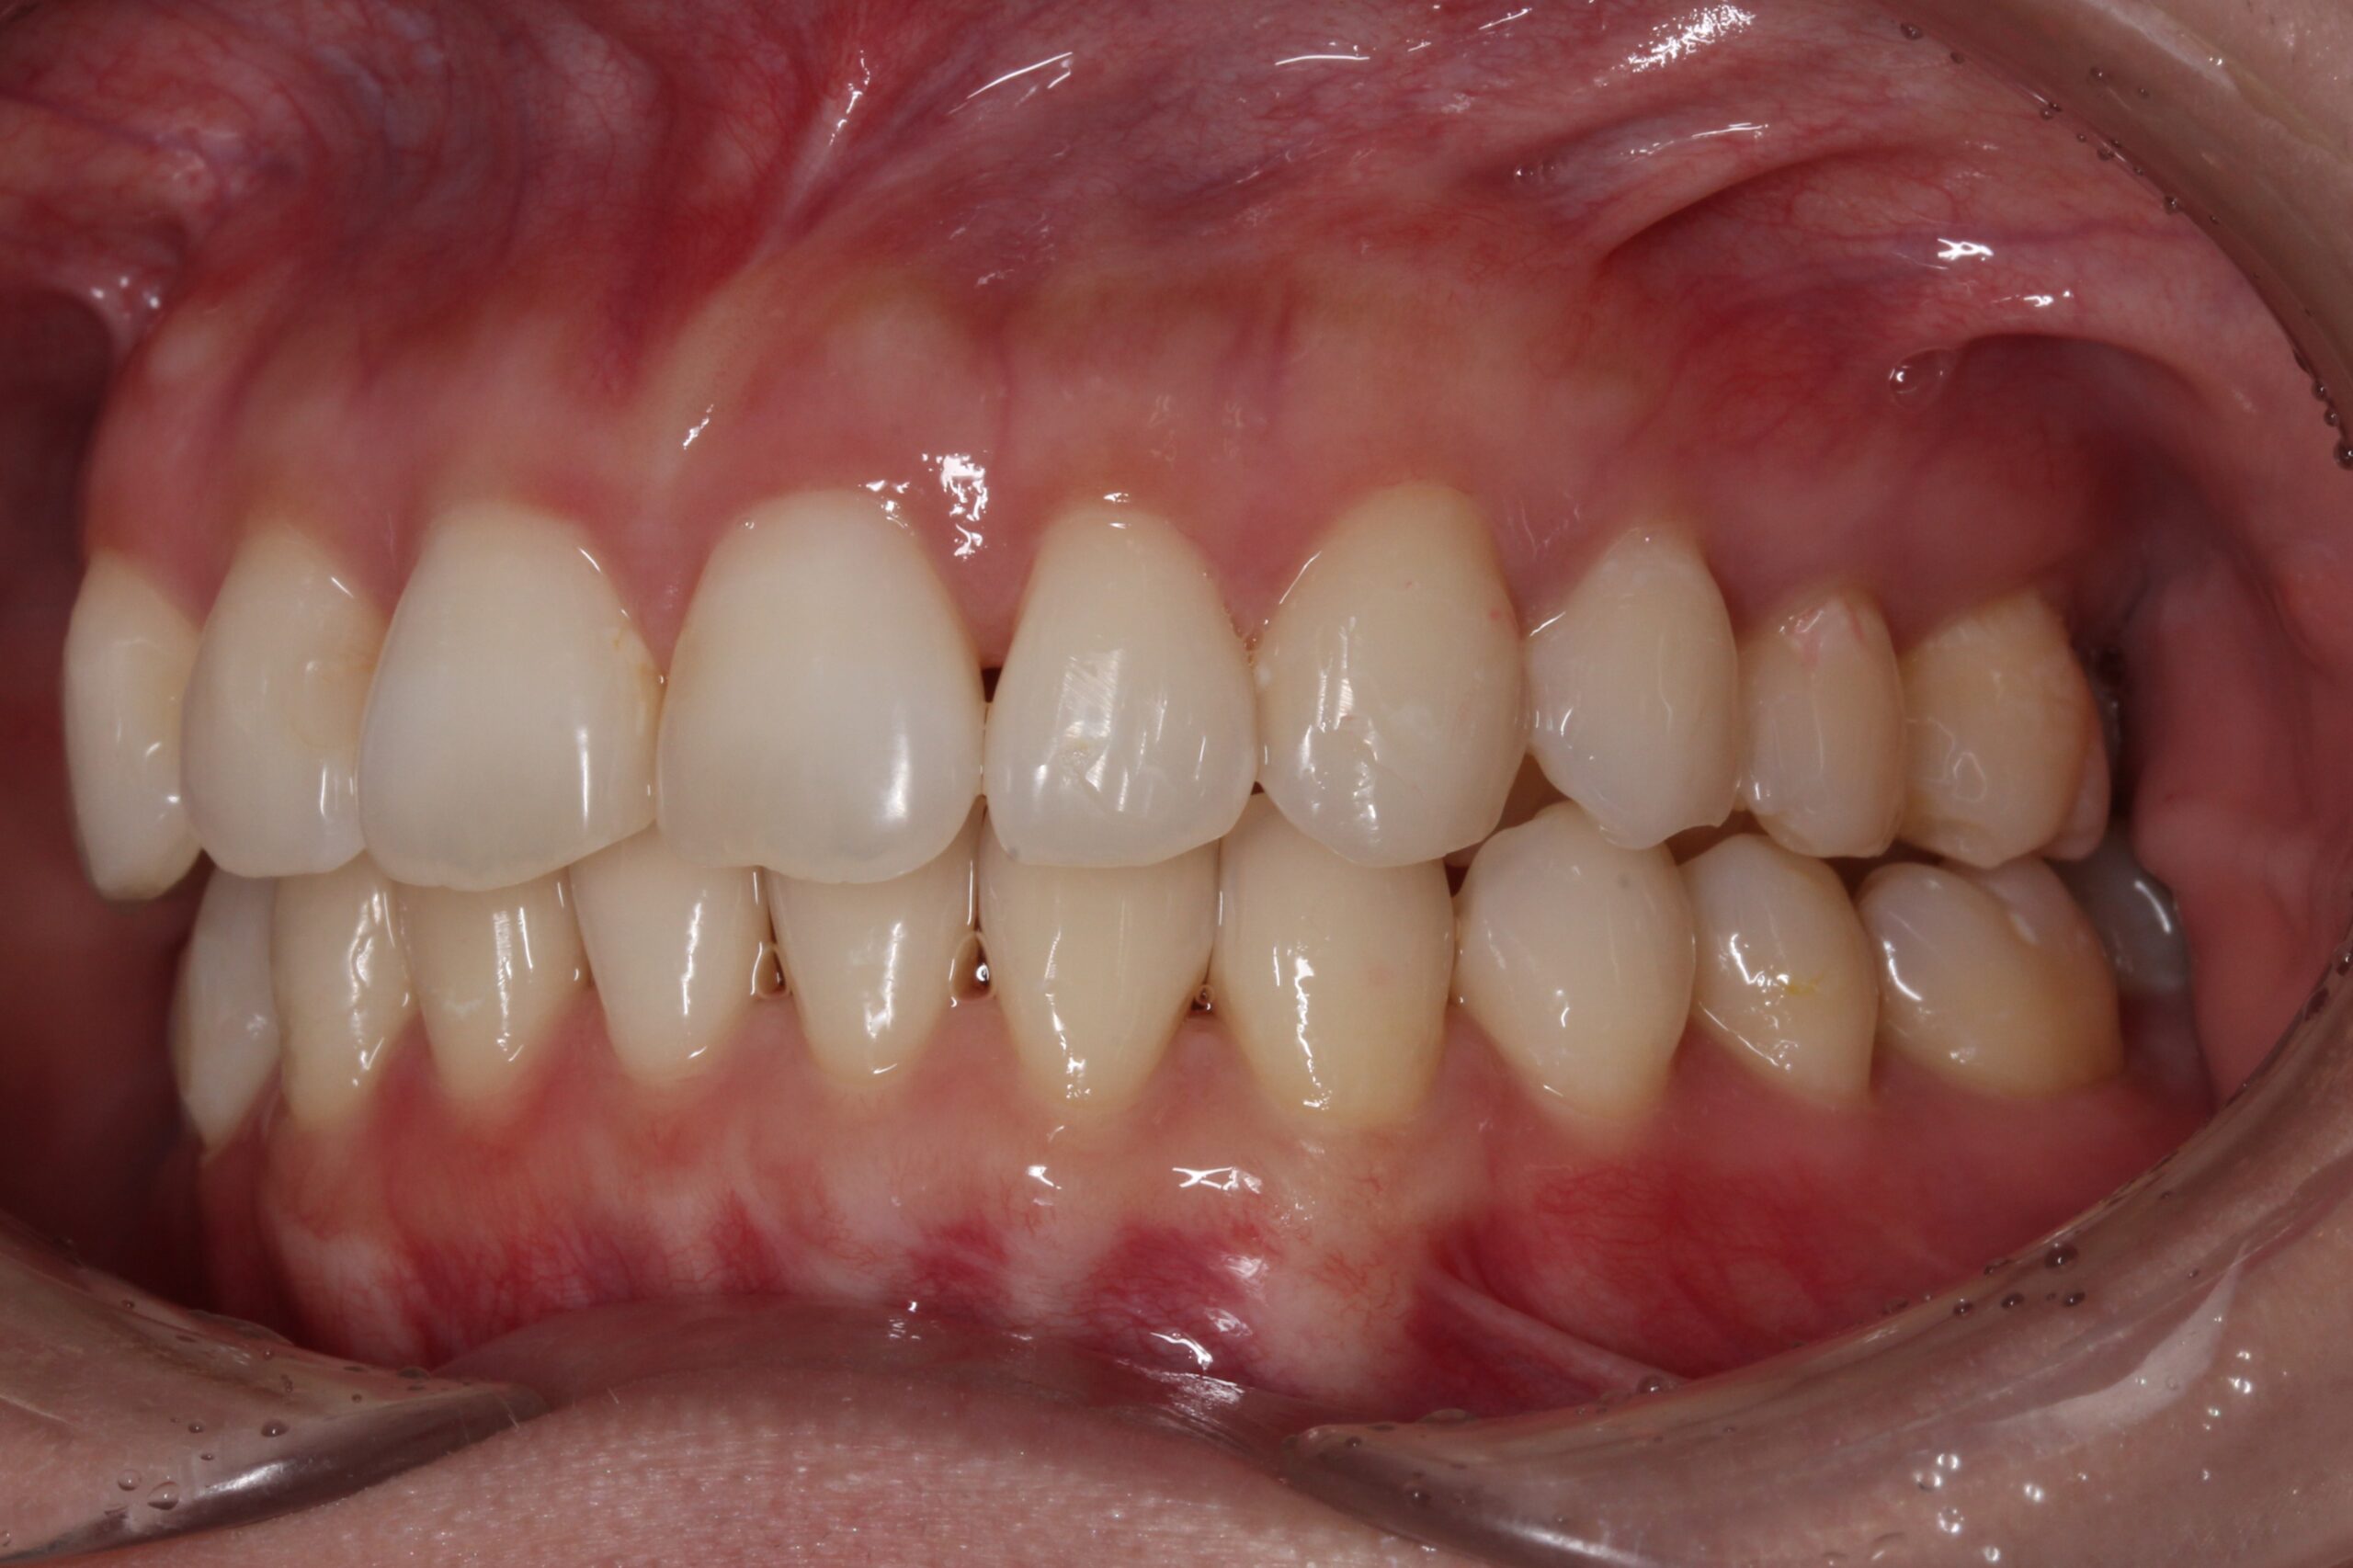

矯正術前:正面

矯正術後:正面